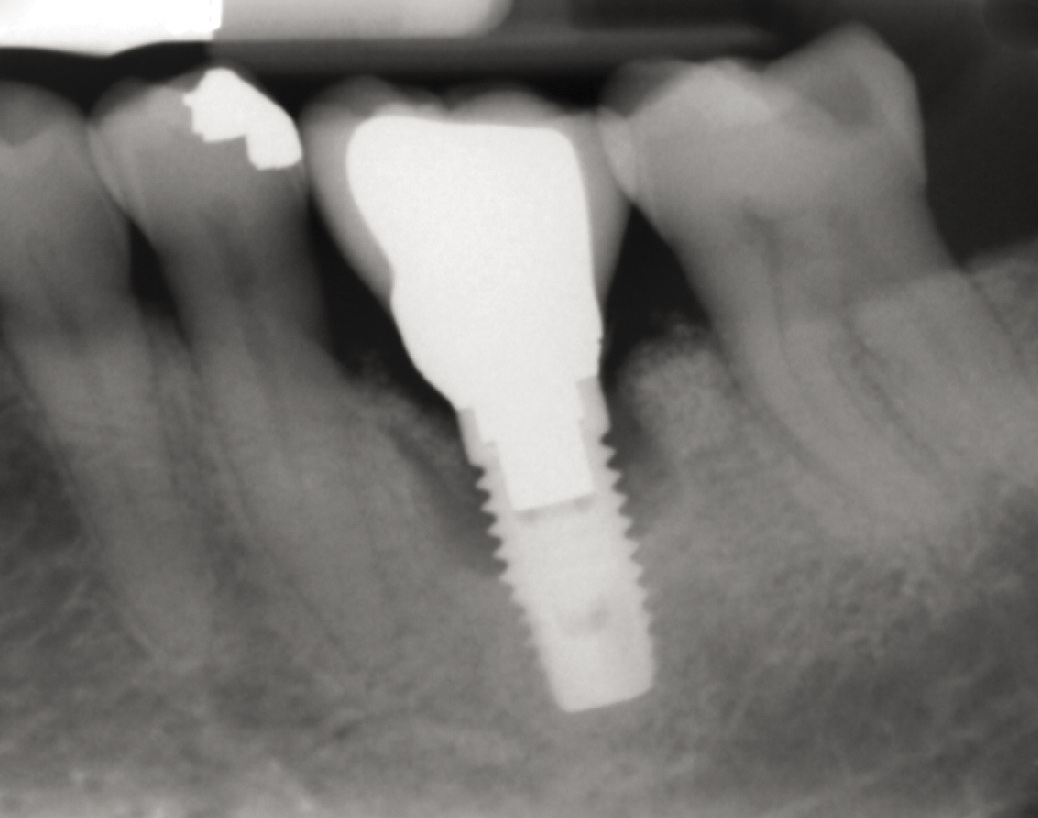

Problem: Implant is placed too close proximally to an adjacent tooth. Forced eruption cannot be performed with the implant in the existing position because the interproximal dimension of the biologic width has been compromised (Figure 47 and Figure 48). Forced eruption without prior implant removal will not gain lost interproximal attachment.9

Fig 47. Implant tooth No. 9 was placed too close proximally to tooth No. 10. The result was violation of interproximal biologic width and loss of interproximal attachment that clinically translated into loss of the interdental papillae.

Fig 48. Radiograph of implant in the area of tooth No. 9 in Figure 47. Note the close proximity of the implant No. 9 to tooth No. 10.